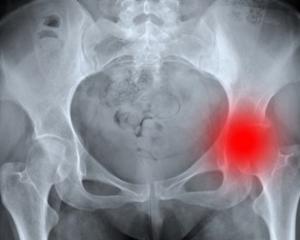

Диагностика коксартроза

Предварительный диагноз можно поставить на основании жалоб, осмотра пациента, во время которого определяют тонус и силу ягодичных, бедренных мышц и мускулов голени, измеряют и объем движений, совершаемых в суставе.

Точный диагноз можно поставить на основании рентгенограммы сустава, выполненной в двух проекциях:

- 1) При I стадии гиперпластический процесс (разрастание) кости незначителен, костные выступы локализуются в вертлужной впадине только с одной стороны вокруг ее суставной поверхности. Бедренная кость интактна. Расстояние между сочленяющимися костями незначительно и неравномерно сужено.

- 2) II стадия: продуктивный процесс наблюдается по обеим краям вертлужной впадины. Развиваются уже и небольшие деформации головки, а также утолщение шейки бедренной кости. Расстояние между головкой бедра и вертлужной впадиной намного меньше нормы, неравномерно.

- 3) При III стадии гиперплазия кости наблюдается уже и со стороны бедренной, и со стороны подвздошной составляющей сустава. Шейка бедра значительно утолщена, а суставная щель, напротив, значительно сужена.